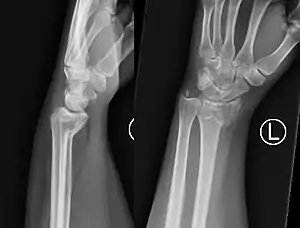

Smith's fracture

A Smith's fracture, is a fracture of the distal radius.[1]

The distal fracture fragment is displaced volarly (ventrally), as opposed to a Colles' fracture which the fragment is displaced dorsally. Depending on the severity of the impact, there may be one or many fragments and it may or may not involve the articular surface of the wrist joint.

Two views should be obtained: AP and lateral.

PA radiography will look very similar to a Colles' fracture, with a fracture along the distal metaphysis of the radius (can be shortened or comminuted). Lateral radiography will demonstrate volar angulation / displacement of the fracture.[6]